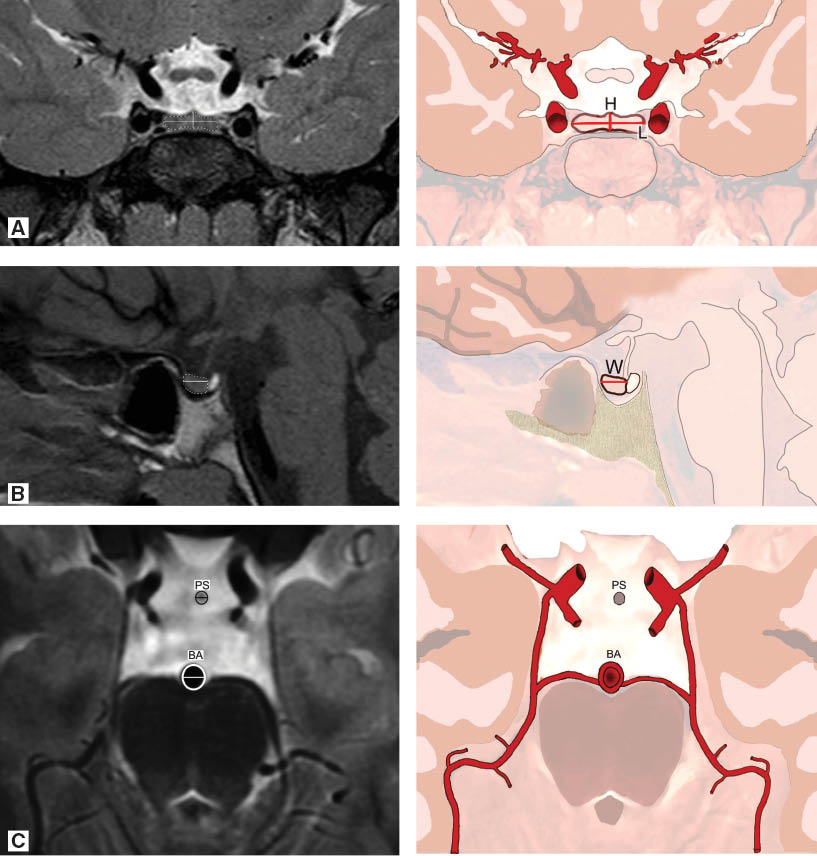

The PG and PS were measured on mid-sagittal and coronal images (Figure 2A). The coronal width and height of PG were evaluated on coronal images. Sagittal width of the PG is shown in Figure 2B. PG volume was calculated with the height×coronal width×sagittal width×0.5 formula (1). The diameters of the PS and BA were measured on axial images on the same plane in the middle of the PS (Figure 2C). PS/BA ratio was calculated.

(A) Height and coronal width of the pituitary gland on coronal plane. (B) Width of the pituitary gland on sagittal plane. (C) Pituitary stalk and basilar artery on axial plane.